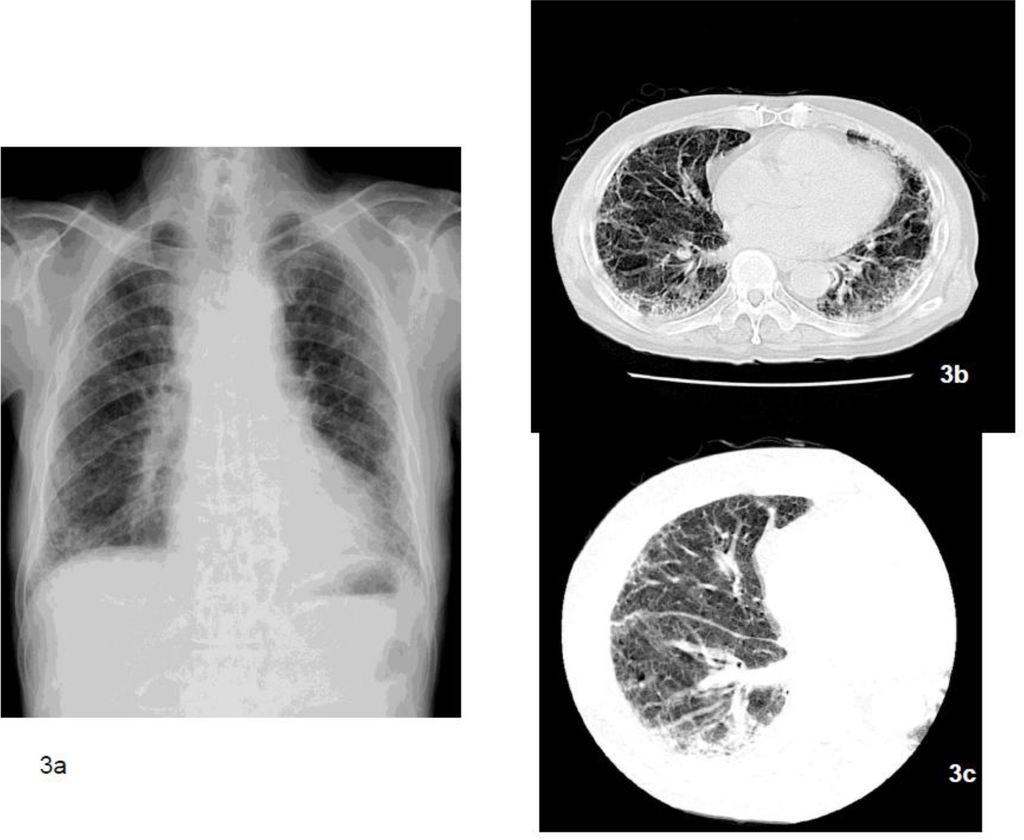

Figure 3.

The chest x-ray (3a) indicates bilateral irregular opacity, and asbestosis was also diagnosed based on occupational asbestos exposure. However, pathologically we could not confirm the diagnosis of asbestosis in this case. The main radiological findings indicated that ground glass shadows (3b, 3c) did not accompany the honeycomb lungs. The fibrosis was observed parallel to the bronchovascular bundle. These were not inconsistent with the diagnosis of asbestosis. However, findings of fibrosis starting from the surrounding area of the bronchioles, which characteristically is the beginning of asbestosis based on pathology, were scarce and evidence of honeycomb lungs was not apparent. Asbestos bodies were sparse inside the lungs and there were 7,482 asbestos bodies/g of dry lung tissue.